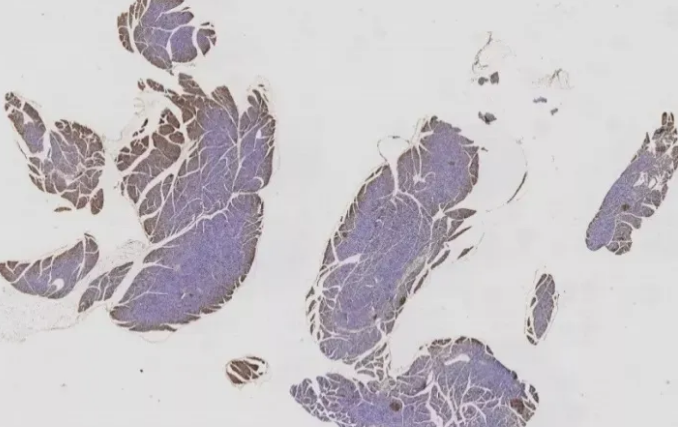

一、固定不充分

10%中性福爾馬林是目前應(yīng)用最廣泛且效果較好的固定方式。組織塊太大,或固定時間太短,都會導(dǎo)致固定不充分。一般8-24h為宜,具體還需要經(jīng)過實際操作摸索確定。如圖1的這種情況,可適當(dāng)延長固定時間到48h。

圖1 固定不充分